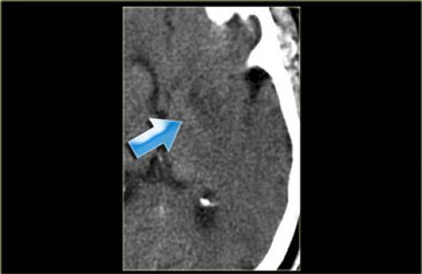

Xuất huyết não nhân bèo, thường gặp ở các bệnh nhân cao huyết áp.

Hình ảnh giảm tỷ trọng nhân bèo, thường liên quan đến nhồi máu động mạch não giữa MCA

Dấu“dải băng thùy đảo”. Hình ảnh này cần được phân biệt với viêm não do Herpes.